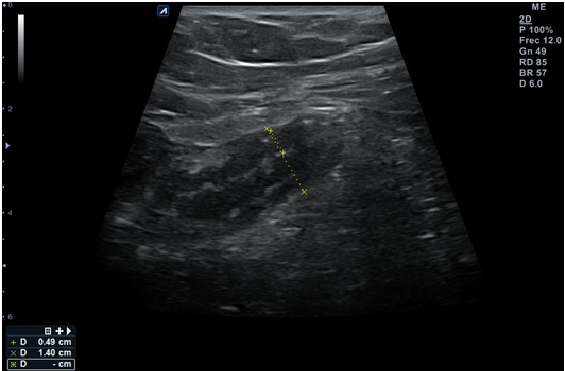

Al día siguiente el paciente acude a su Centro de Salud ya que persiste el dolor abdominal localizado en flanco derecho. A la exploración física destaca dolor la palpación fosa ilíaca derecha (FID) siendo más intenso a la descompresión. Se realiza ecoscopia dirigida con sonda lineal de alta frecuencia donde se visualiza en FID lo que parece un apéndice engrosado (14 milímetros), hipoecogénico, con paredes gruesas (hasta 5 milímetros) no compresible, grasa mesentérica periapendicular hiperrefrigente que se moviliza en bloque y pequeña cantidad de líquido libre periapendicular, con Blumberg ecográfico positivo. (Imagen 1)